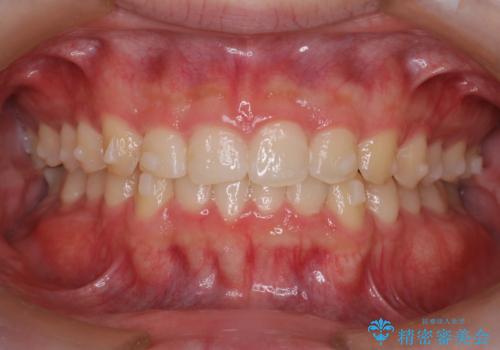

【インビザライン】前歯のガタガタと、前歯の噛み合わせが深いことを治したい。

- 前歯のガタガタと、前歯の噛み合わせが深いことを治したい。との主訴で来院されました。

シミュレーションを用いながら患者様と仕上がりについて相談しインビザラインにて治療を行いました。

仕上げは追加アライナーを数回利用しておこないました。